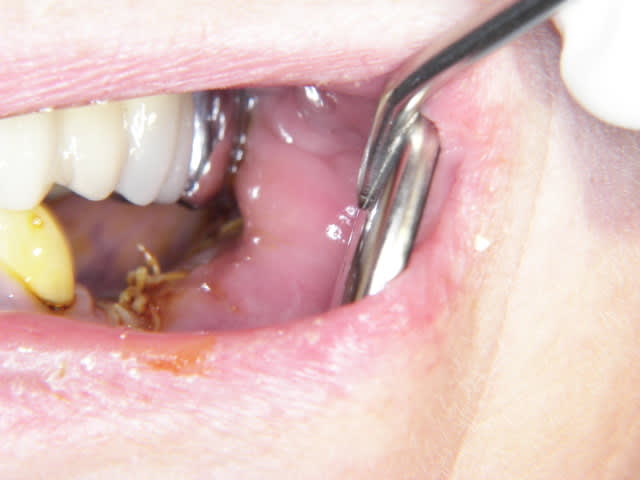

panoramique et photo pas de suite post op pas d'hematome, pas de douleur YESSSS

implants dans 5 mois si tvb